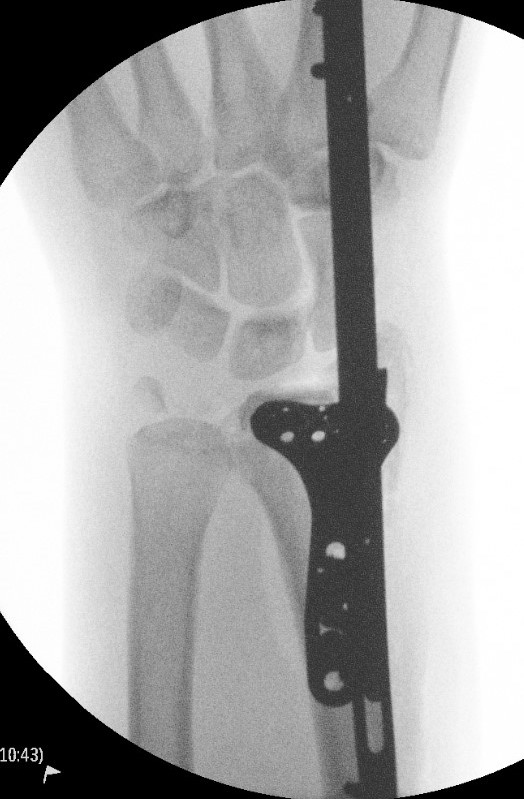

Dorsal distraction plating

Indication

Internal radiocarpal distraction

- unreconstructable distal radius fractures

- early weight bearing in poly trauma patients

- osteoporotic bone

Advantage - no pin site infection from external fixation

Disadvantage - need to remove plate at 3 - 4 months once fracture united

Technique

Extended dorsal approach

- protect sensory radial nerve

- open 3rd extensor compartment / retract EPL radially

- mobilized 4th extensor compartment / retract EDC ulnarly

- bare area of radius proximally between EDC and ECRB / ECRL

Fixation to 2nd or 3rd metacarpal first

- 2nd metacarpal: under 2nd extensor compartment

- 3rd metacarpal: under 4th extensor compartment

- reduce / distract joint

- +/- additional radius fixation